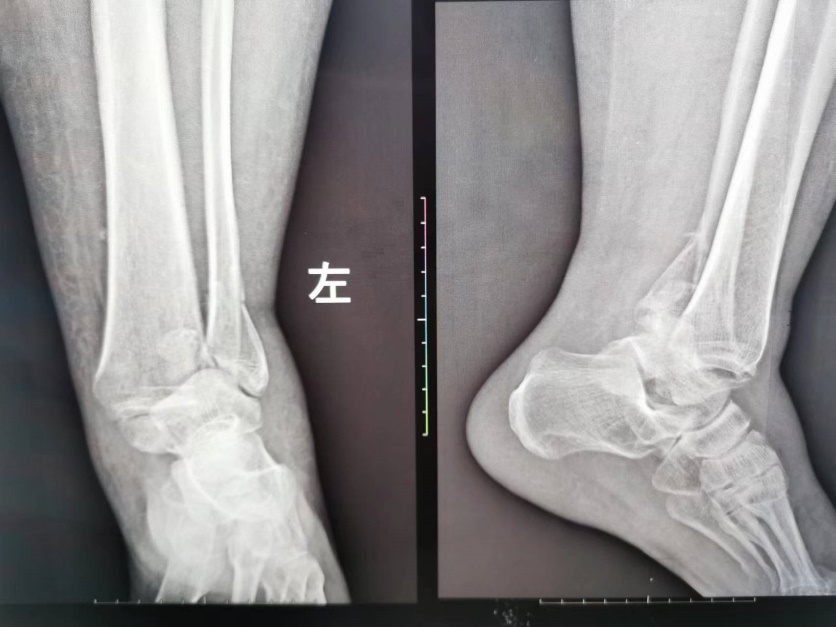

病例五:患者,女,56岁,因“车祸伤致左踝关节肿痛伴活动受限14小时”入院。诊断:左侧三踝粉碎性骨折伴踝关节脱位;行左踝关节骨折切开复位内固定术;手术顺利,术后进行康复训练中,功能恢复良好。

左侧三踝粉碎性骨折 术前X线片